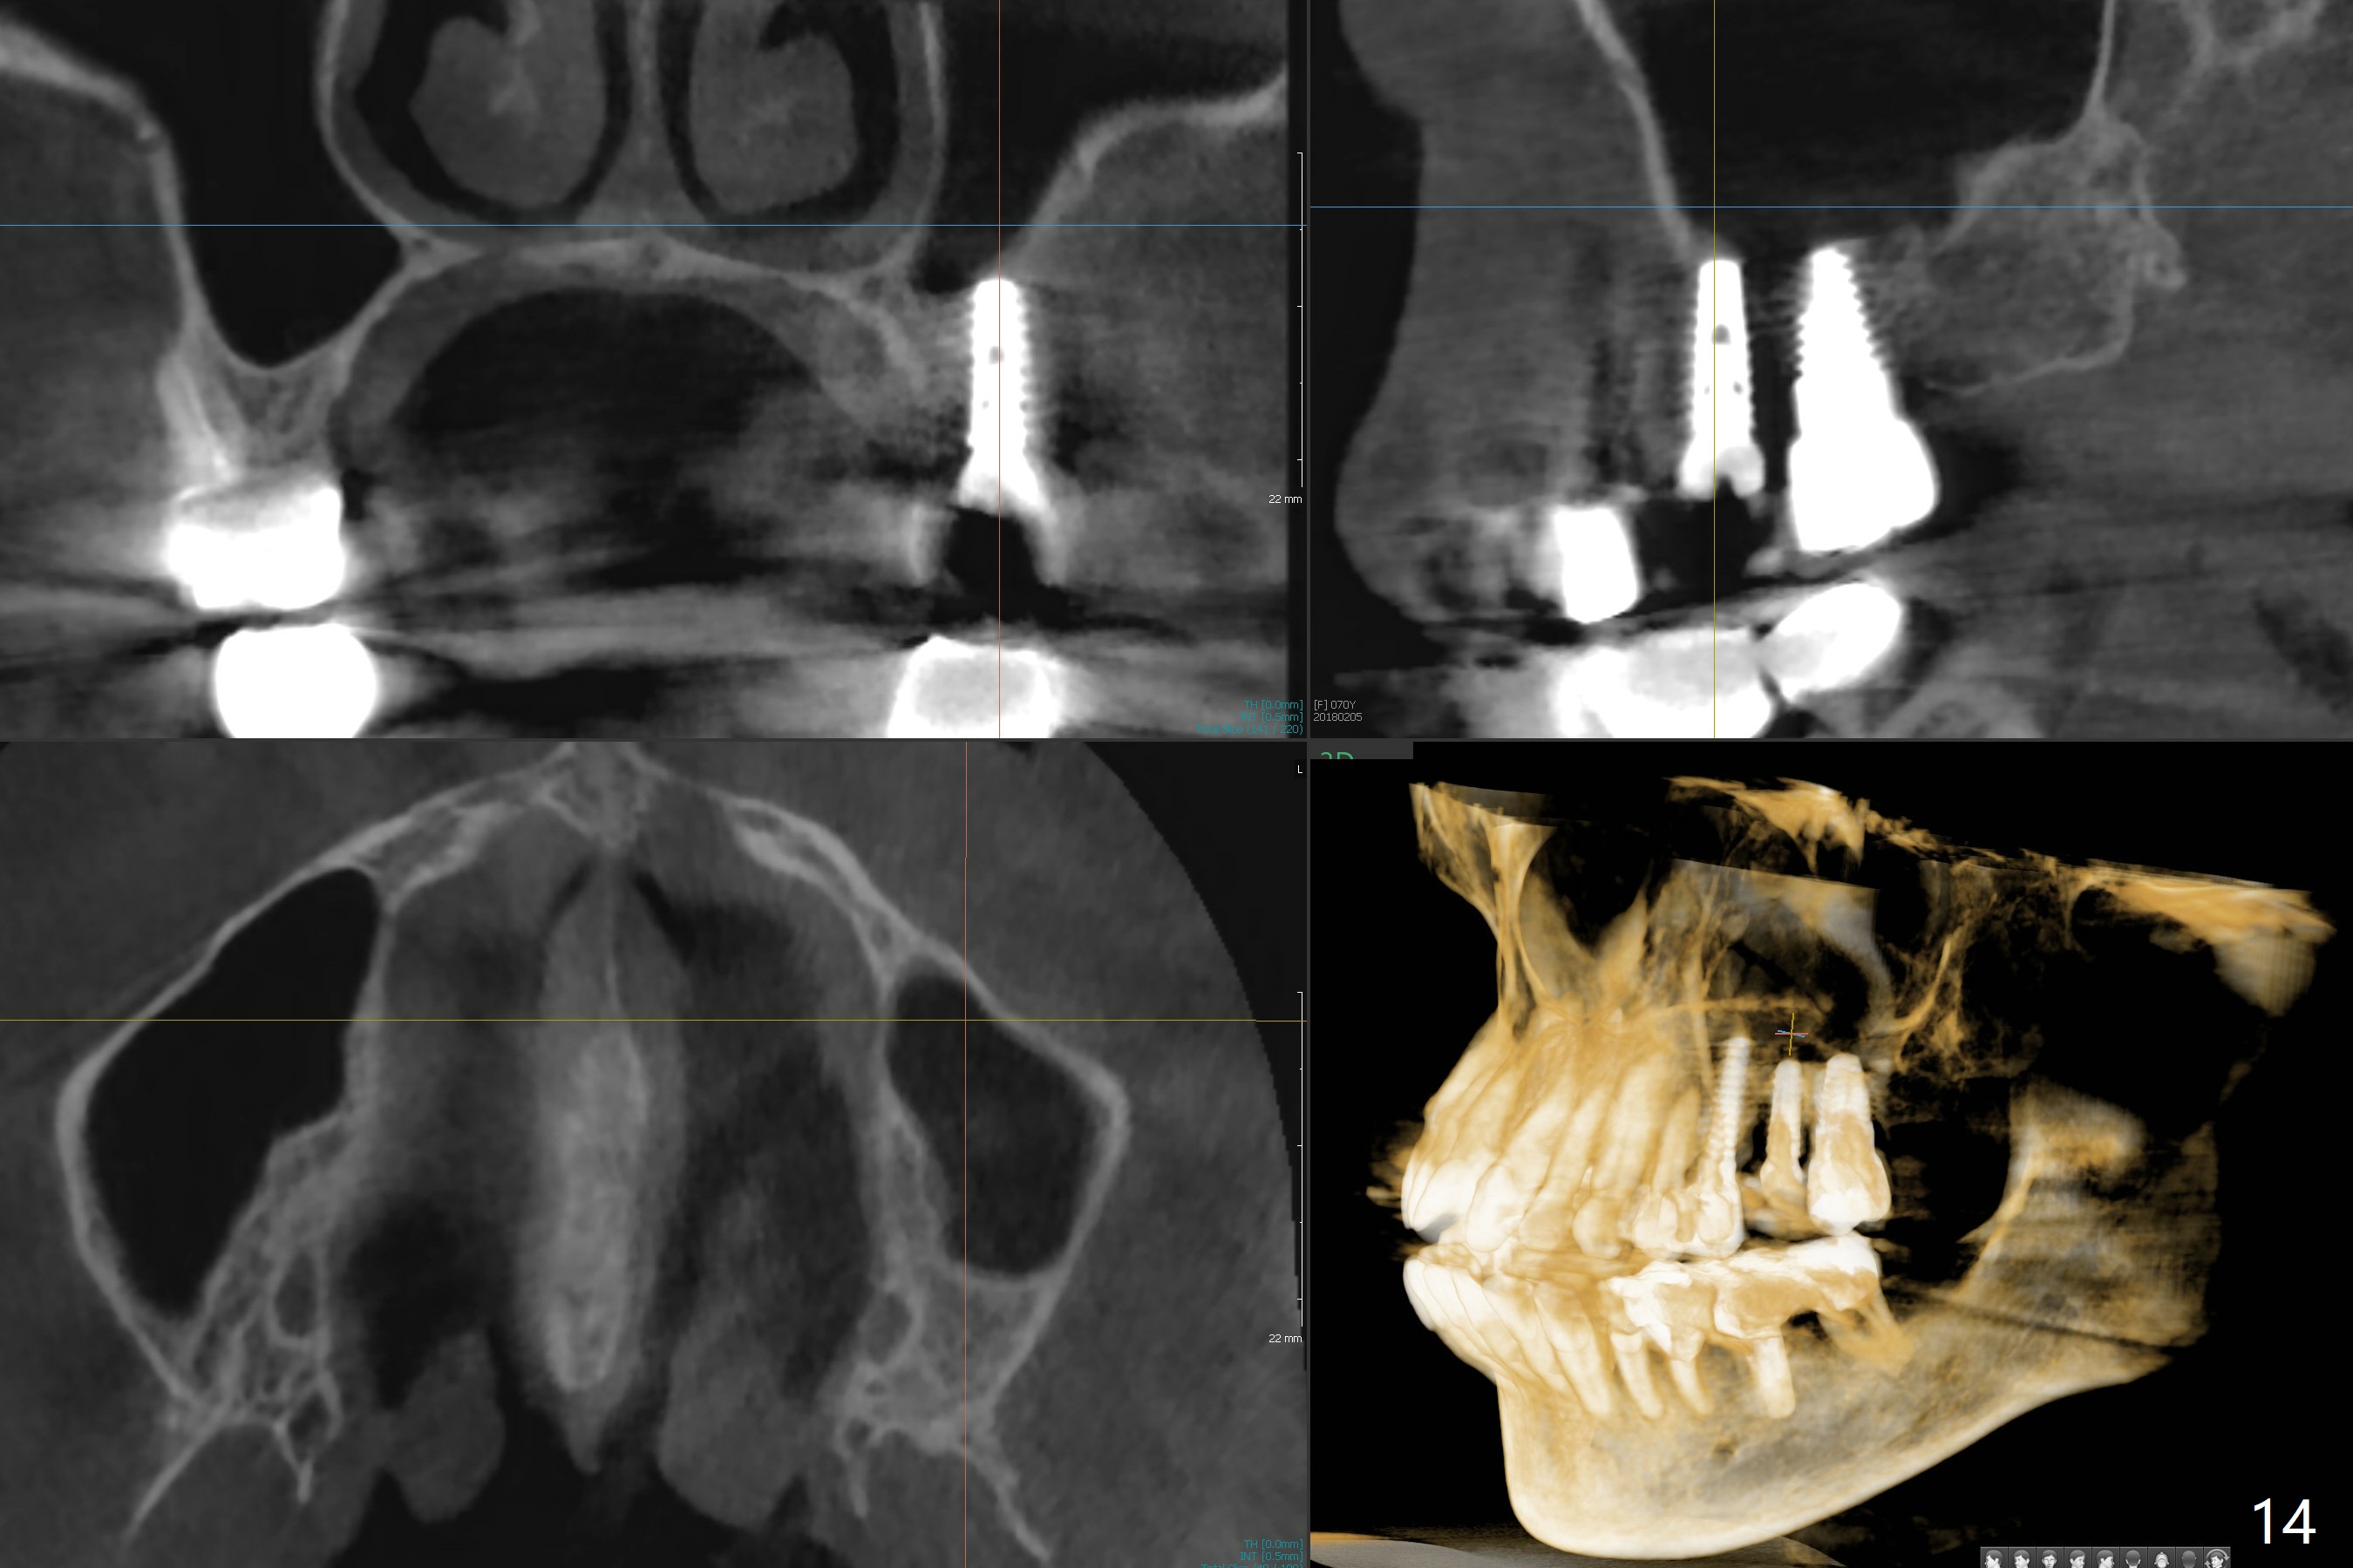

Initial osteotomy in the septum of the tooth #14 is 9 mm, approximately 2 mm from the sinus floor (Fig.1). Subsequent osteotomy depth is 11 mm, followed by insertion of a 4.5x11 mm dummy implant (Fig.2). After use of Magic Drill (MD) 4.8 mm for 9 mm, a 5x11 mm IBS implant is placed with sinus lift without additional bone graft (Fig.3 *). In contrast, autogenous bone (from MD) and Vanilla Graft are meticulously placed in the remaining socket (+) before and after placement of a 6.5x5.7(2) mm abutment. An immediate provisional is fabricated to close the sockets. There is buccal tenderness 1-3 months postop. There is distopalatal implant thread exposure. A healing abutment (5.5x2 mm) is placed. CT confirms thin buccal plate (Fig.4,5). It appears that the implant should have been as palatal as possible. The tenderness remains for the next 2 weeks. When the healing abutment is removed, the implant seems to have been placed shallow, ~ 1 mm subgingival (Fig.6). With local anesthesia, the implant is reversed to clean the coronal threads with Titanium brush and copious irrigation (Fig.7). The implant is then placed ~4 mm subgingival (Fig.8) and slightly subcrestal (Fig.9,10). It appears that the postop bone loss (Fig.9 *, as compared Fig.1,2) makes the implant look to be placed too shallow. When the implant is being placed deeper, the buccal plate feels intact. The early periimplantitis is apparently due to postop bone loss more than buccal placement, although certain degree of buccal bone resorption must occur. A 6x4 mm healing abutment is placed. Left facial swelling develops 2 days post implant elevation (Fig.11,12, as compared to preop (Fig.13)). The left maxillary sinus cloud (Fig.12) appears to be a false positive finding, since the same feature exists prior to implant elevation (Fig.13). Both sinuses look clear prior to implant elevation (Fig.14). Amoxicillin switches to Augmentin and Flagyl, since the patient is reluctant to have the implant removed. Finally the sinus infection is under control. The patient feels left facial swelling 9 months postop (5 months post elevation) and reports left nasal discharge ~ 1 month earlier. There is mild buccal plate tenderness. The implant seems to be buccally placed (Fig.15,16), although there is no significant change radiographically (Fig.17). The implant is removed with bone graft (Fig.18 *). To avoid complication and failure, an immediate implant at the upper 1st molar should be short and placed deep.